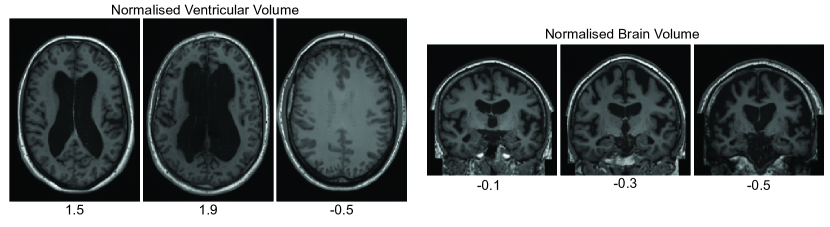

Refer to caption

Figure 2: Conditioned sampling varying the ventricular volume and the brain volume normalized by the intracranial volume. In both rows, we kept the other variables constant.

Using the hybrid conditioning approach [23], we were able to condition our models and generate brain images where we can specify the age, sex, ventricular volume, and brain volume. As we can observe in Fig. 2, our model was able to learn representations conditioned on regional (i.e., ventricular volume) and global (i.e., brain volume) volumes.

Finally, we verified how our model extrapolates the conditioning variables for values never shown during training. Fig. 4 presents samples where we used a normalised ventricular value higher than 1; in this case, we can see abnormally huge ventricles when using values of 1.5 and 1.9. If we use a negative value (e.g., -0.5), an image without ventricles is generated. Similarly, if we use negative values for the brain normalised for head size, the brain exhibits signs of neurodegeneration, showing smaller volumes of white and grey matter. These findings suggest that our models learned the concepts behind these conditioning variables during training.

Figure 4: Extrapolating values of conditioning variables. During the training of the models, the inputted values of the conditioning variables were scaled between 0 and 1. In this experiment, we tried values outside of this range, and we observed that our model could extrapolate the representation of brain and ventricular volumes, showing that it learned the concept of these variables.